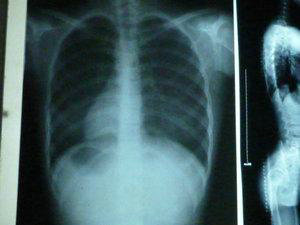

(图:李先生2013年拍的X光片)

【检查治疗】

接诊的是崔丽主任,根据李先生的检查报告制定了适合他自己的治疗方案。

(图:治疗后李先生检查结果明显好转)

连续四次治疗后,李先生自述各方面感觉比以前好很多,除了一个融合的关节,其它地方和正常人都没有区别了。以前弯腰的时候,手只能碰到膝盖,现在可以碰到小腿了;